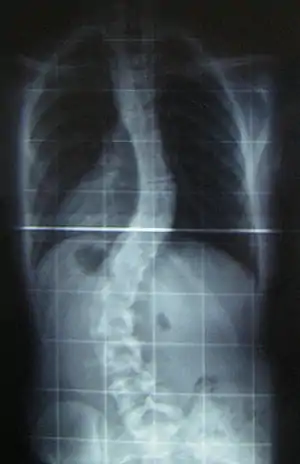

| رادیوگرافی از یک کژپشتی | |